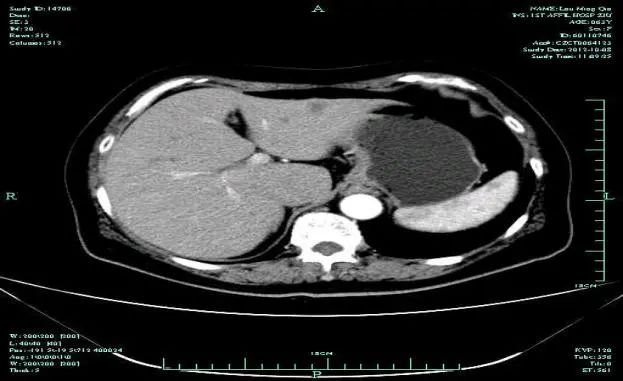

CT-T

CT-H1

影像学检查结果评估:cPD。